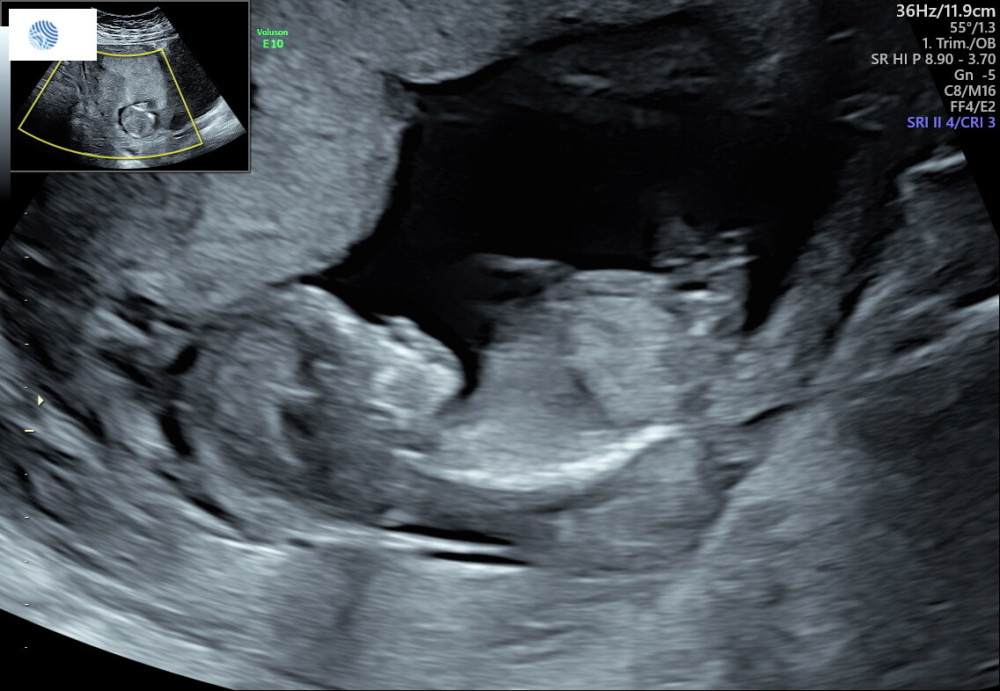

Huhu, ich mach auch mal mit beim Ratespielchen - war heute bei der NFM - der Vertretungsarzt wollte sich nicht äußern - weiß nicht, ob das was ich mir denke wirklich der NUB ist, aber sollte das dieser sein, würde ich persönlich jetzt auf Mädchen tippen. Ich mach das allerdings zum ersten Mal und könnte auch sein, dass ich komplett daneben liege und man sieht den hier gar nicht Was sagt ihr?